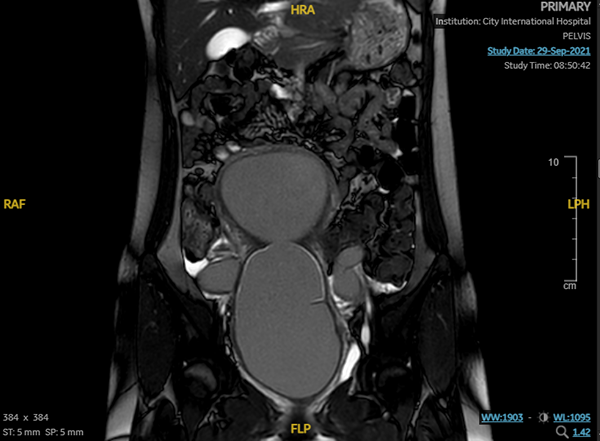

Hình chụp trước sau – A: Phần âm đạo ứ máu. B phần tử cung ứ máu